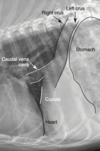

On lateral radiographs, the right diaphragmatic crus can be identified by its:

A) Association with the gastric fundus

B) Confluence with the caudal vena cava

C) Attachment to the left kidney

D) Connection with the thoracic duct

A

B

3

confluence of the CVC with the right crus of the diaphragm - in RL this will be the cranial crus